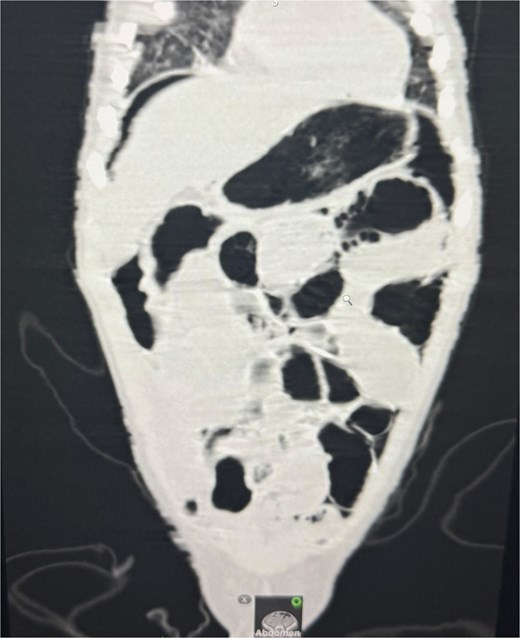

An abdominal X-ray, erect, and computed tomography (CT) abdomen revealed free subdiaphragmatic air, suggestive of hollow viscus perforation (Fig. 1). Exploratory laparotomy was performed, which revealed an inflamed, edematous, ischemic ascending colon with a solitary perforation leaking fecal matter (Fig. 2). Enlarged mesenteric lymph nodes were present, while the appendix and rest of the bowel appeared normal. A right hemicolectomy with side-to-side ileocolic anastomosis was performed. The resected specimen, comprising ileum, cecum, appendix, and ascending colon, on histopathology revealed acute on chronic nonspecific ileitis with typhlitis and colitis, complicated by cecal perforation (Fig. 3).

CT abdomen revealed free air under the diaphragm, indicating hollow viscus perforation.